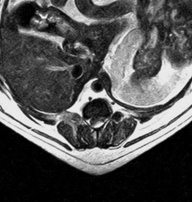

転移性脳腫瘍